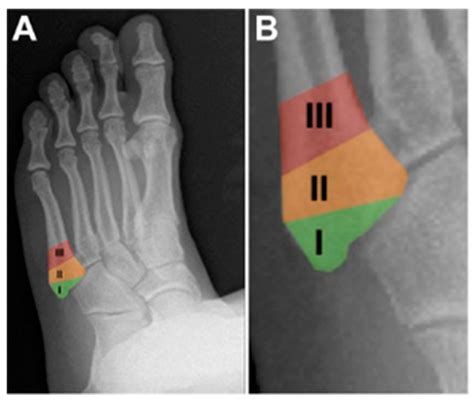

A Pseudo Jones Fracture is a specific type of fracture that occurs in the fifth metatarsal bone of the foot. This bone is located on the outer side of the foot and connects to the little toe. The term "Pseudo Jones" distinguishes it from a true Jones fracture, which occurs at the base of the fifth metatarsal. A Pseudo Jones Fracture typically involves a fracture at the proximal diaphysis of the fifth metatarsal, just distal to the tuberosity.

• Order X-rays to visualize the fracture and determine its location and severity.

Pseudo Jones Fracture Proximal diaphysis of the fifth metatarsal Sudden impact, twisting, or rolling the ankle Non-surgical (RICE, immobilization), Surgical (ORIF, bone grafting)

Jones Fracture Base of the fifth metatarsal Sudden impact, twisting, or rolling the ankle Non-surgical (RICE, immobilization), Surgical (ORIF, bone grafting)